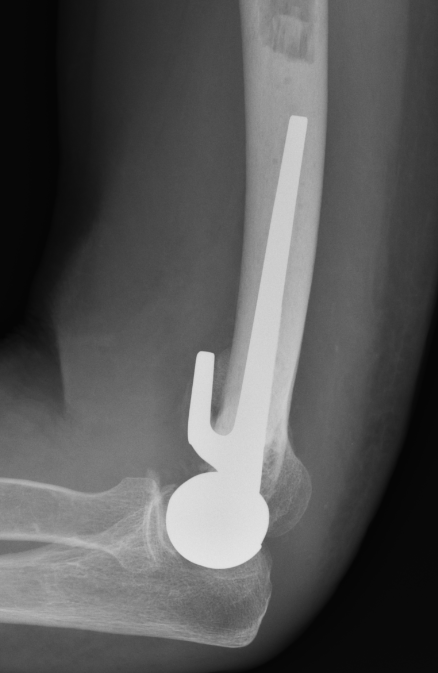

Comminuted coronal shear fracture in elderly patient treated with distal humerus replacement